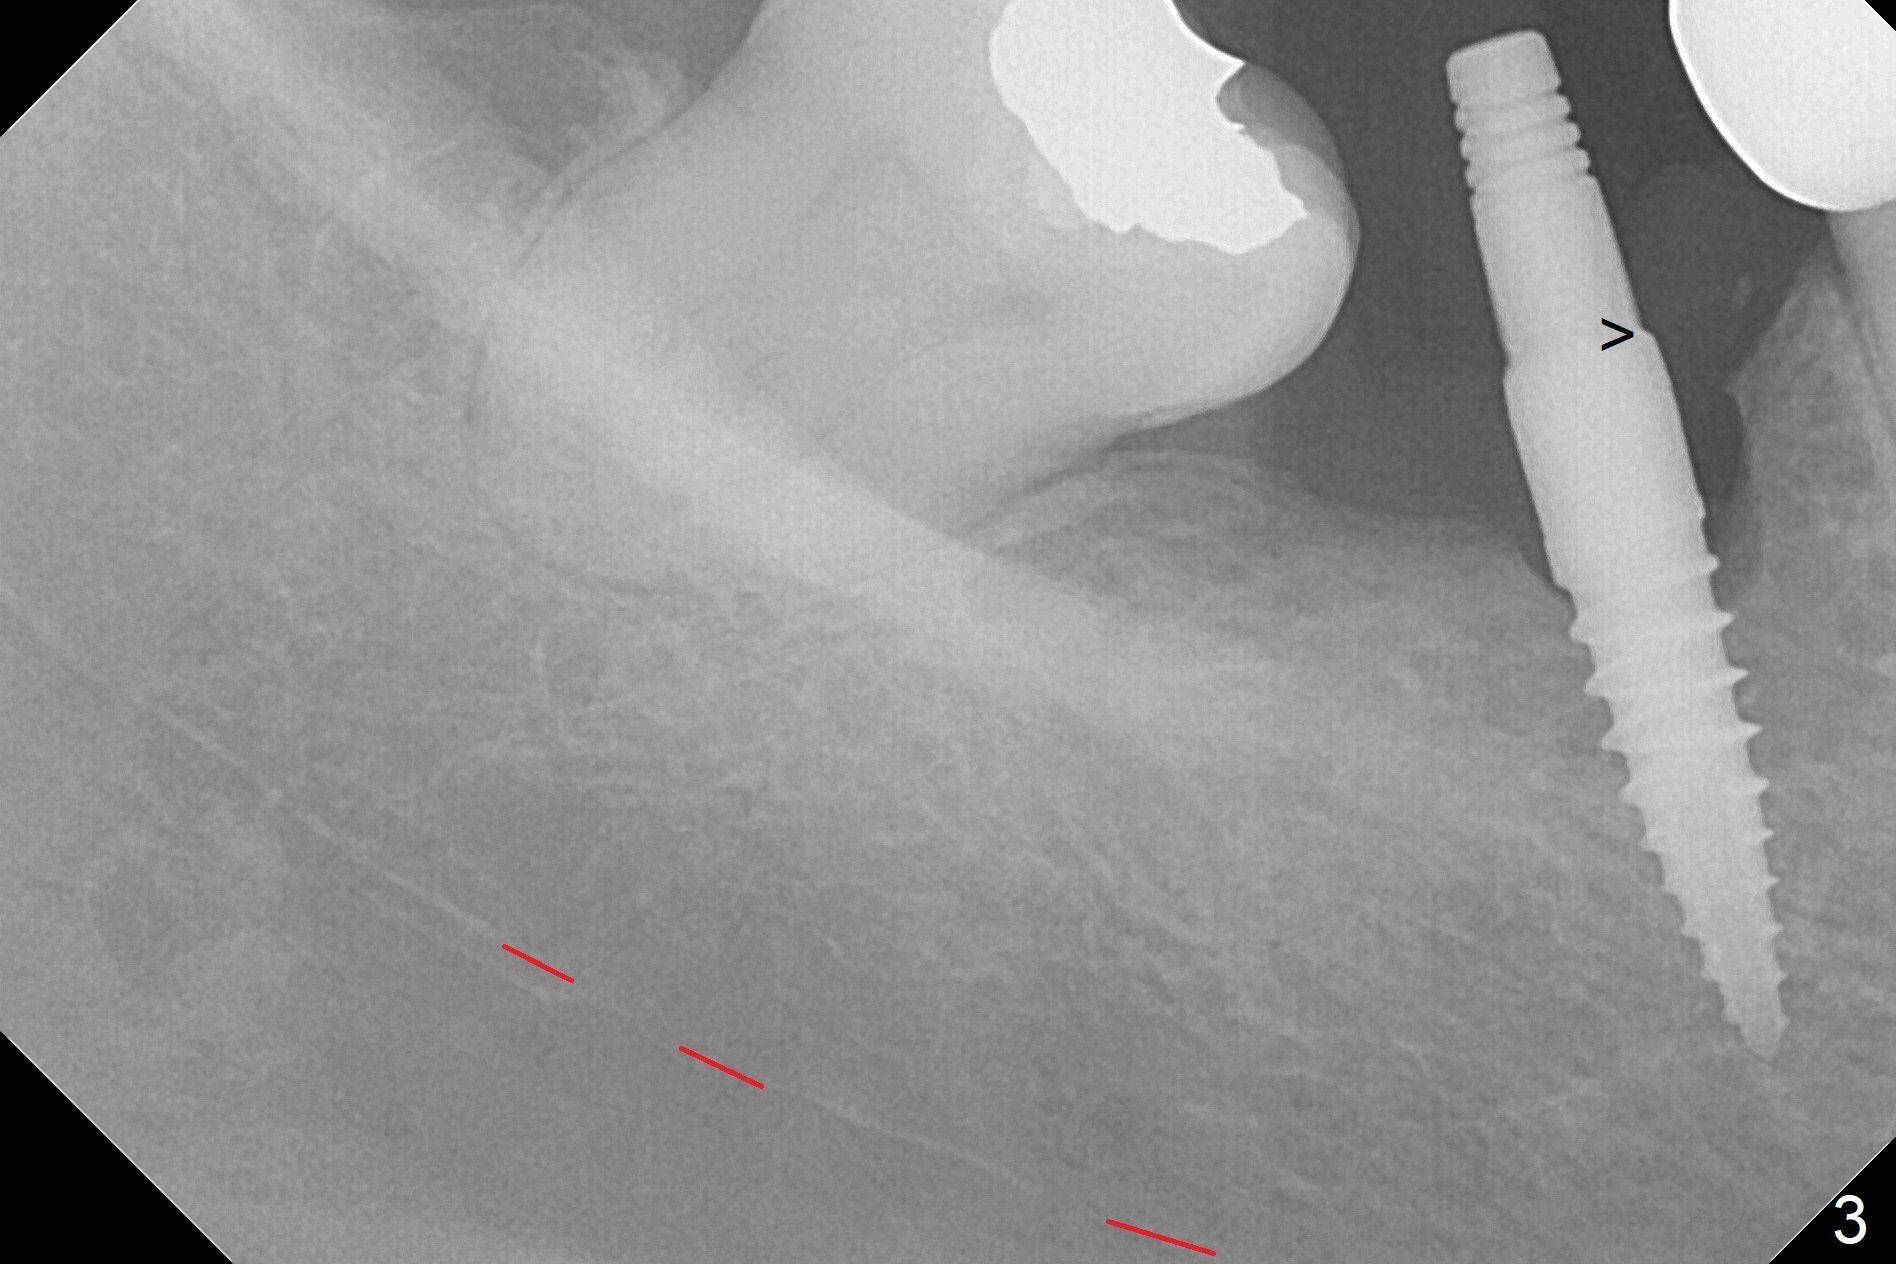

Incision reveals a narrow ridge and a narrow mesiodistal space at #30 (Fig.1).  It seems that a 1-piece implant is indicated.  Due to limited mouth opening, a 1.2 mm drill is unstable in place after use for 10 mm; instead a 1.5 mm drill is able to be inserted for 8 mm (Fig.2).  A 3x10(2) mm 1-piece dummy implant is placed with 40 Ncm at an apparently acceptable level (Fig.3 >).  Clinically a few threads are exposed buccally.  When a definitive implant with the same dimension is inserted with 45 Ncm, it looks seated too deep (Fig.4,5).  The latter is noted after suturing.  The implant is backed up for a few turns so that the length of the abutment appears a little more reasonable.  Introspectively, a 4 mm cuff should have been used after ridge reduction.  Although there is no bone loss 4 months postop (Fig.6), the abutment margin (Fig.7 arrow) is subgingival (red dashed line: gingival margin).  Diode laser is used for gingivectomy prior to impression.  The bone density around the implant increases 11 months post cementation (Fig.8 *), probably related to recurrent #18 infection.  The patient uses floss after meal.